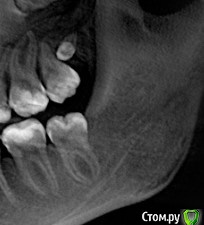

L.E.S.I.K. Опубликовано 21 марта, 2016 Поделиться Опубликовано 21 марта, 2016 Интересный и редкий случай сегодня попался. Пациент 58 лет. Жалобы на то, что "прорезавшиеся" зубы в ментальном отделе мешают пользоваться съемным протезом. На лицо все признаки ключично-черепного дизостоза (хотя ранее диагноз не устанавливался.) Удалил зубы в ментальном отделе( кроме "лежащего" премоляра справа - много для доступа пришлось бы кости убирать,побоялся перелома) и гнилые корешки.8-ки не трогал по той же причине,тем более они не визуализируются в полости рта и пациент на них не жалуется.http://s017.radikal.ru/i409/1603/c6/9275a61b825e.jpghttp://s018.radikal.ru/i514/1603/4b/8e634c76a43c.jpghttp://s017.radikal.ru/i430/1603/3f/af56bb779752.jpg 10 Ссылка на комментарий

L.E.S.I.K. Опубликовано 22 марта, 2016 Поделиться Опубликовано 22 марта, 2016 Ето что за ... незнаю названия?Если Вы спрашиваете, каков диагноз, то это наследственное заболевание- ключично-черепной дизостоз (болезнь Шейтхауэра-Мари-Сентона), одним из симптомов которого является гипердентия и множественная ретенция зубов. Ссылка на комментарий